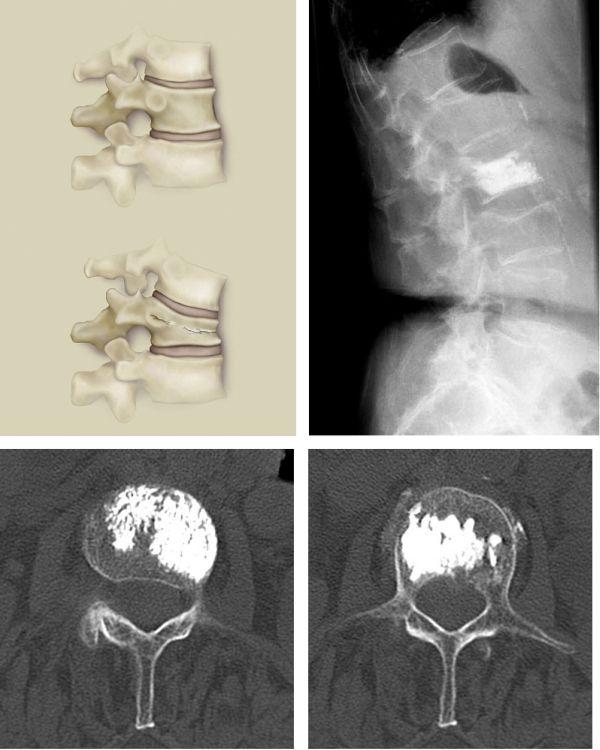

Vertebroplastie

Die Vertebroplastie stellt ein minimal invasives Verfahren zur Behandlung von schmerzhaften Wirbelkörperkompressionen dar. Eine Nadel wird unter Röntgenkontrolle durch die Haut in den komprimierten Wirbelkörper eingeführt. Über diese Nadel wird zähflüssiger Knochenzement in den Wirbelkörper eingebracht, der dort innerhalb weniger Minuten aushärtet. Danach kann der Wirbel wieder belastet werden, die Schmerzen sind in aller Regel sofort beseitigt. Die Behandlung wird in der Regel in Vollnarkose durchgeführt, ist aber grundsätzlich auch in örtlicher Betäubung möglich.